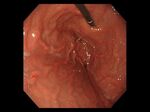

要確認、あなたは「ピロリ菌」に感染していないか?